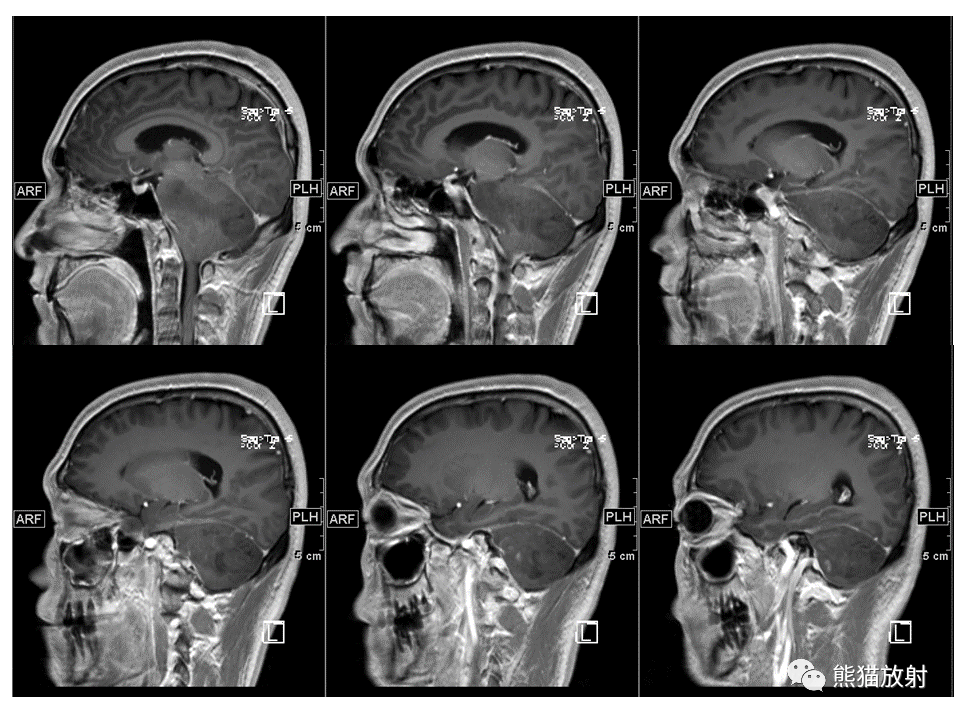

【PPT】小脑发育不良性神经节细胞瘤 VS 成人型髓母细胞瘤-3